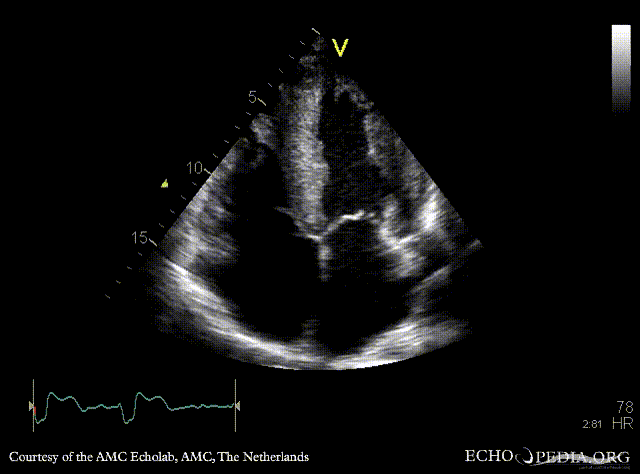

Amyloidosis

A4CH: concentric left and right ventricle hypertrophy with reduced systolic function, biatrial enlargement Subcostal view: concentric left and right ventricle hypertrophy